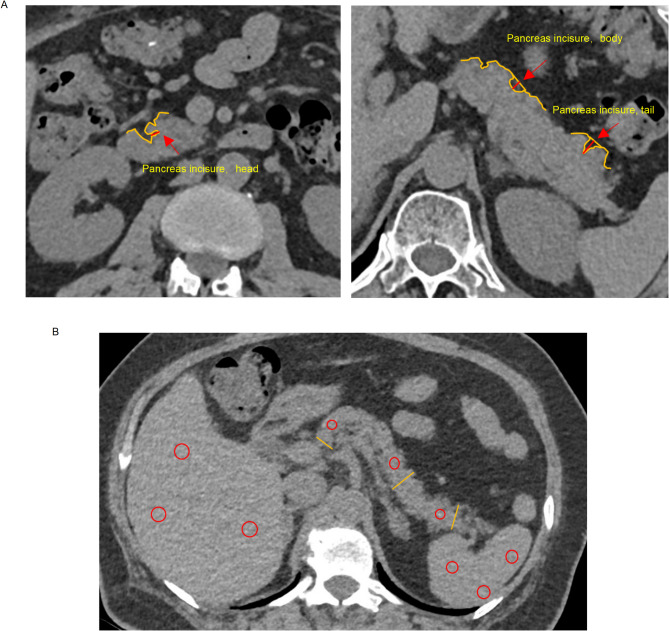

{"title":"计算机断层扫描显示胰腺切口深度增加是T2DM的独立预测指标。","authors":"Yilong Huang, Zhangwaner Yao, Yongchun Zeng, Junjie Hua, Ning Yao, Zhixiao Luo, Zhibo Xiao, Qian Ge","doi":"10.1038/s41598-025-08193-x","DOIUrl":null,"url":null,"abstract":"<p><p>We aim to identify CT-based biomarkers in the pancreas for predicting both the presence and prognosis of T2DM. Between January and December 2021, a population of 2246 subjects undertaken health-check were recruited. Between January 2023 and June 2024, another 244 hospitalized patients with T2DM were recruited. Depth of pancreas incisure (DPI), CT attenuation, and thickness were measured using an unenhanced CT scan. Compared to individuals without T2DM, DPI was significantly increased in subjects with T2DM, regardless of whether they were of normal weight or obese. After adjusting for age, sex, BMI, waist circumference, lipid, liver function, and hepatic fat content, DPI remained independently associated with the presence of T2DM. However, no significant difference in DPI was observed between T2DM patients without insulin deficiency [Fasting C-peptide (FCP) ≥ 0.6 ng/ml] and those with absolute insulin deficiency (FCP < 0.6 ng/ml). DPI was not associated with the presence of absolute insulin deficiency; conversely, reduced pancreatic thickness was independently associated with this condition. Additionally, our findings did not reveal any significant association between pancreatic fat content and T2DM. Increased DPI may serve as a potential biomarker for predicting the risk of T2DM, whereas reduced pancreatic size may indicate a poorer prognosis for this disease.</p>","PeriodicalId":21811,"journal":{"name":"Scientific Reports","volume":"15 1","pages":"23389"},"PeriodicalIF":3.9000,"publicationDate":"2025-07-02","publicationTypes":"Journal Article","fieldsOfStudy":null,"isOpenAccess":false,"openAccessPdf":"https://www.ncbi.nlm.nih.gov/pmc/articles/PMC12222510/pdf/","citationCount":"0","resultStr":"{\"title\":\"Increased depth of pancreas incisure on computed tomography as an independent predictor for T2DM.\",\"authors\":\"Yilong Huang, Zhangwaner Yao, Yongchun Zeng, Junjie Hua, Ning Yao, Zhixiao Luo, Zhibo Xiao, Qian Ge\",\"doi\":\"10.1038/s41598-025-08193-x\",\"DOIUrl\":null,\"url\":null,\"abstract\":\"<p><p>We aim to identify CT-based biomarkers in the pancreas for predicting both the presence and prognosis of T2DM. Between January and December 2021, a population of 2246 subjects undertaken health-check were recruited. Between January 2023 and June 2024, another 244 hospitalized patients with T2DM were recruited. Depth of pancreas incisure (DPI), CT attenuation, and thickness were measured using an unenhanced CT scan. Compared to individuals without T2DM, DPI was significantly increased in subjects with T2DM, regardless of whether they were of normal weight or obese. After adjusting for age, sex, BMI, waist circumference, lipid, liver function, and hepatic fat content, DPI remained independently associated with the presence of T2DM. However, no significant difference in DPI was observed between T2DM patients without insulin deficiency [Fasting C-peptide (FCP) ≥ 0.6 ng/ml] and those with absolute insulin deficiency (FCP < 0.6 ng/ml). DPI was not associated with the presence of absolute insulin deficiency; conversely, reduced pancreatic thickness was independently associated with this condition. Additionally, our findings did not reveal any significant association between pancreatic fat content and T2DM. Increased DPI may serve as a potential biomarker for predicting the risk of T2DM, whereas reduced pancreatic size may indicate a poorer prognosis for this disease.</p>\",\"PeriodicalId\":21811,\"journal\":{\"name\":\"Scientific Reports\",\"volume\":\"15 1\",\"pages\":\"23389\"},\"PeriodicalIF\":3.9000,\"publicationDate\":\"2025-07-02\",\"publicationTypes\":\"Journal Article\",\"fieldsOfStudy\":null,\"isOpenAccess\":false,\"openAccessPdf\":\"https://www.ncbi.nlm.nih.gov/pmc/articles/PMC12222510/pdf/\",\"citationCount\":\"0\",\"resultStr\":null,\"platform\":\"Semanticscholar\",\"paperid\":null,\"PeriodicalName\":\"Scientific Reports\",\"FirstCategoryId\":\"103\",\"ListUrlMain\":\"https://doi.org/10.1038/s41598-025-08193-x\",\"RegionNum\":2,\"RegionCategory\":\"综合性期刊\",\"ArticlePicture\":[],\"TitleCN\":null,\"AbstractTextCN\":null,\"PMCID\":null,\"EPubDate\":\"\",\"PubModel\":\"\",\"JCR\":\"Q1\",\"JCRName\":\"MULTIDISCIPLINARY SCIENCES\",\"Score\":null,\"Total\":0}","platform":"Semanticscholar","paperid":null,"PeriodicalName":"Scientific Reports","FirstCategoryId":"103","ListUrlMain":"https://doi.org/10.1038/s41598-025-08193-x","RegionNum":2,"RegionCategory":"综合性期刊","ArticlePicture":[],"TitleCN":null,"AbstractTextCN":null,"PMCID":null,"EPubDate":"","PubModel":"","JCR":"Q1","JCRName":"MULTIDISCIPLINARY SCIENCES","Score":null,"Total":0}

We aim to identify CT-based biomarkers in the pancreas for predicting both the presence and prognosis of T2DM. Between January and December 2021, a population of 2246 subjects undertaken health-check were recruited. Between January 2023 and June 2024, another 244 hospitalized patients with T2DM were recruited. Depth of pancreas incisure (DPI), CT attenuation, and thickness were measured using an unenhanced CT scan. Compared to individuals without T2DM, DPI was significantly increased in subjects with T2DM, regardless of whether they were of normal weight or obese. After adjusting for age, sex, BMI, waist circumference, lipid, liver function, and hepatic fat content, DPI remained independently associated with the presence of T2DM. However, no significant difference in DPI was observed between T2DM patients without insulin deficiency [Fasting C-peptide (FCP) ≥ 0.6 ng/ml] and those with absolute insulin deficiency (FCP < 0.6 ng/ml). DPI was not associated with the presence of absolute insulin deficiency; conversely, reduced pancreatic thickness was independently associated with this condition. Additionally, our findings did not reveal any significant association between pancreatic fat content and T2DM. Increased DPI may serve as a potential biomarker for predicting the risk of T2DM, whereas reduced pancreatic size may indicate a poorer prognosis for this disease.